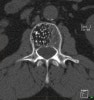

CT : 뼈의 밀도 변화를 민감하게 찾아낼 수 있으므로 척추의 작은 병변뿐만 아니라 주변 연부조직의 병변도 감지할 수 있습니다.

CT : Polka dot appearance

진단 : Bone scan, CT